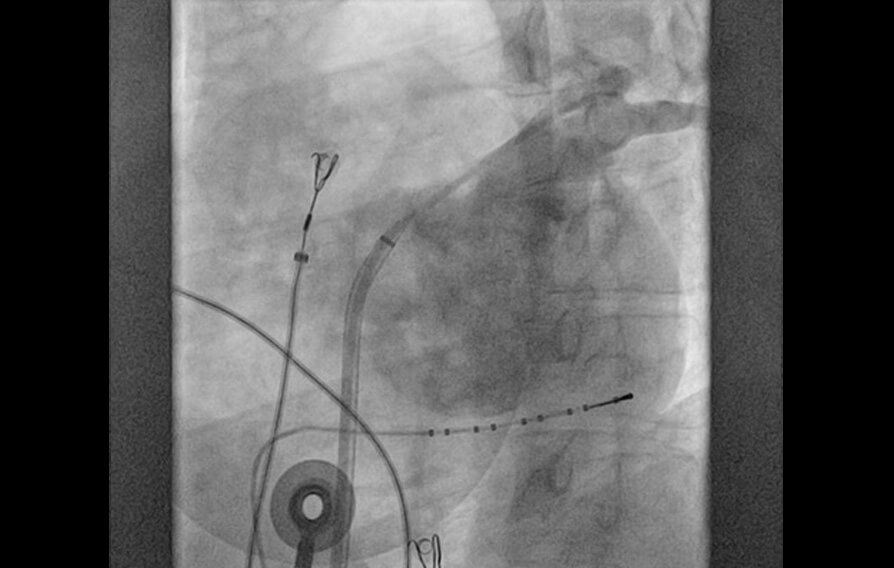

El tratamiento por cateterismo de las arritmias suele realizarse con la aplicación de calor que elimina el foco que produce la arritmia. La crioablación, por el contrario, aplica frío para congelar el foco arritmogénico. La aplicación de frío es más segura y previene lesiones irreversibles. Gracias a esta tecnología, podemos tratar con seguridad arritmias localizadas en zonas del corazón muy cercanas a estructuras importantes que de otro modo tendrían riesgo de ser dañadas.